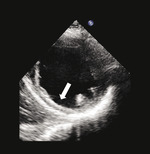

Rycina 1. Spoczynkowe przezklatkowe badanie echokardiograficzne (projekcja przymostkowa w osi krótkiej i zmodyfikowana projekcja koniuszkowa) u pacjenta po rozległym zawale ściany dolnej przebytym 5 lat wcześniej. Ściana dolna charakteryzuje się znacznym zmniejszeniem grubości końcoworozkurczowej (5 mm, strzałki), co wskazuje na obecność blizny i nieodwracalnego uszkodzenia